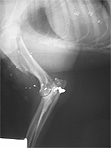

Na fotografiji rentgenograma je lepo viden zlom nadlahtnice, ter večji in manjši delci izstrelka. Na "srečo" krogla ni poškodovala sklepa, ker bi v nasprotnem primeru pes ostal trajni invalid, saj mu zdrobljenega sklepa skoraj gotovo ne bi mogli sanirati. | |